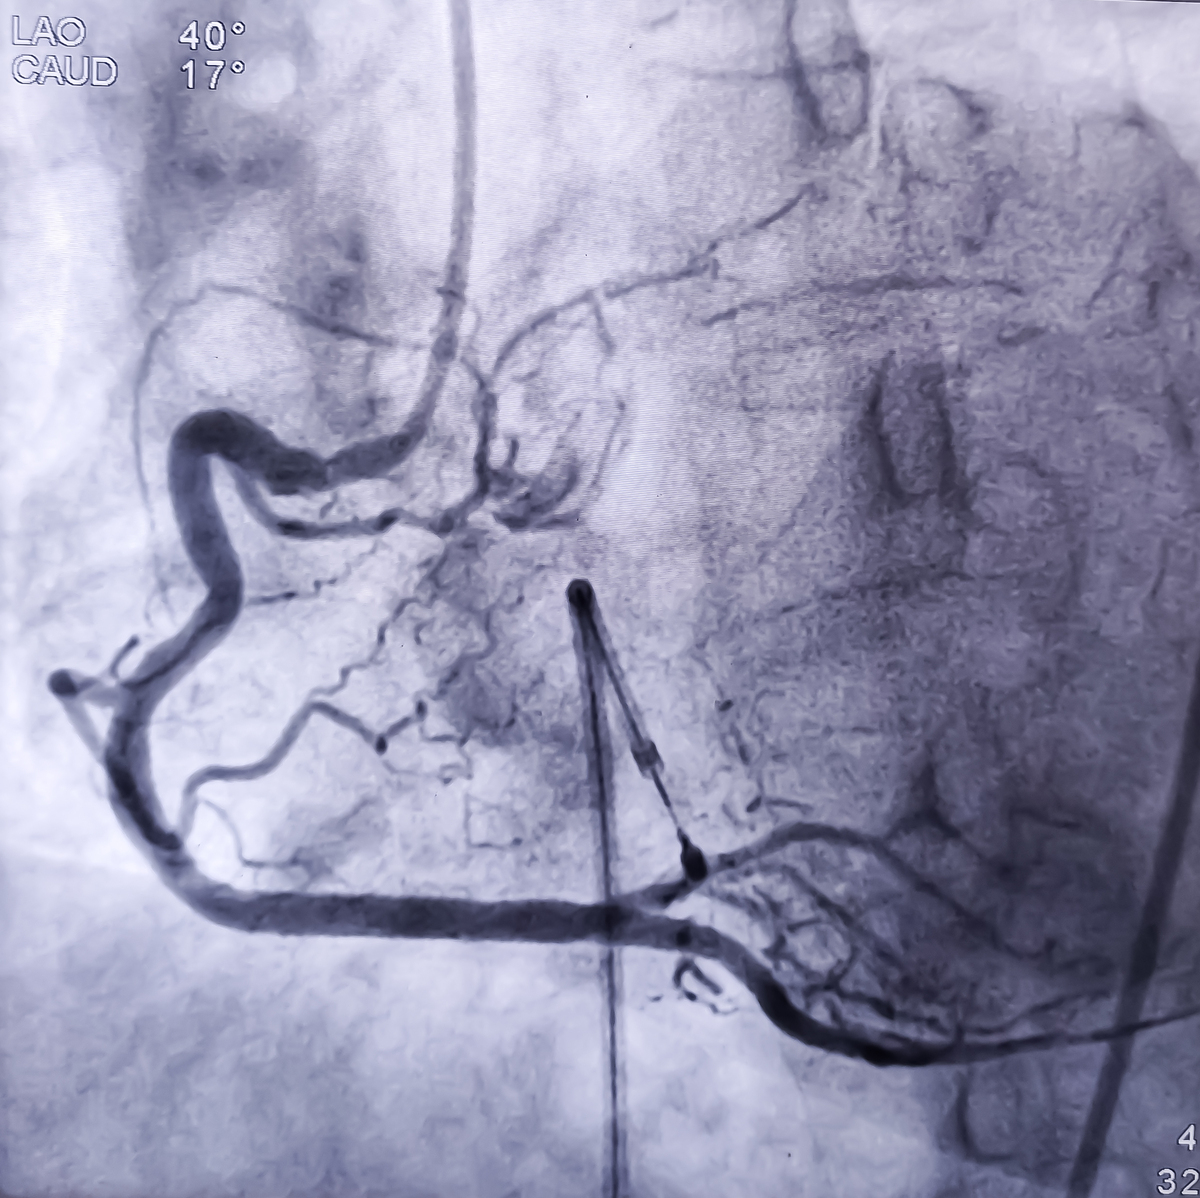

3. 内窥镜下冠状动脉支架植入术(PCI):在 PTCA 的基础上,再将支架放入狭窄或阻塞的冠状动脉内,以维持血管的通畅。